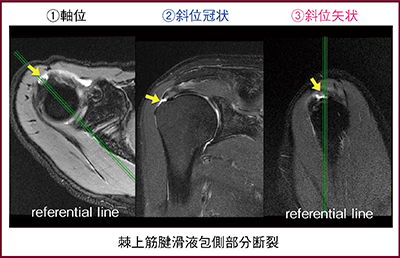

軸位断撮像では,肩鎖関節を十分に入れて腋窩までを垂直に撮像し,角度のついていない軸位断を得ることでchain oblique現象を回避できる。次に,肩甲骨平面と上腕骨頭の長軸をつないだ線を斜位冠状断の基準線とする。斜位矢状断は,肩甲骨平面に対して直交して撮像するため,結果的に関節窩に平行となる。斜位冠状断(図1)と斜位矢状断にreferential lineを表示しながら腱板断裂を読影しても,chain oblique現象で画像が回転することなく,referential lineも各平面に正しく投影される。

図1 斜位冠状断とreferential line